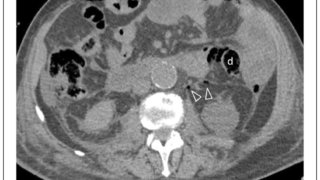

手術日+552日目 2025/9/2(火)(椎体再骨折)

午前の病院での仕事と腰椎椎体骨折後再骨折の急患今朝は晴れていました. 湿度は低くて, 爽やかな朝でした. しかし, 今日も最高気温は35 ℃超の木書美となる予報でした.8時前に病棟に上がりました. 早速, 夜勤の看護師さんから, 昨日亡くな...